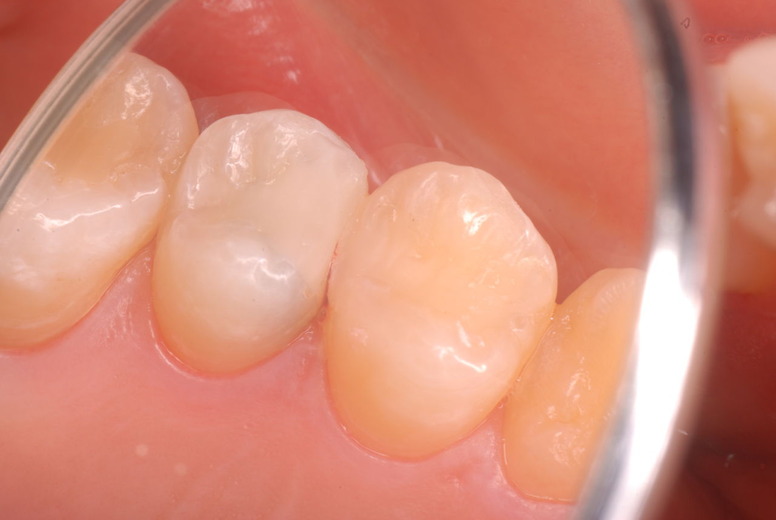

歯周病になっていましたが、少し色が黄色くなっているだけで比較的綺麗な歯の状態です。

平成9年来院神経を取り、同時に歯周病の話をしてそのまま来なくなっていたかたですが、たまたま一部欠けてきました。それで来院。

平成24年一部欠けて来院

15年前と同じように詰めて終了。磨き方はまあまあでした。でも問題少ないでしょう。![ea7f9628-s[1]](https://livedoor.blogimg.jp/netdental/imgs/c/2/c2ef91be.jpg)

虫歯という病気を完全に治し、神経の処置で神経の病気を治し、ブラシの使い方をマスターすれば歯やお口の中は問題を起こしにくいのです。何かを被せることは注意が必要ですし、歯を傷つける訳ですからブラシの使い方をマスターしてから被せないと危ないのです。